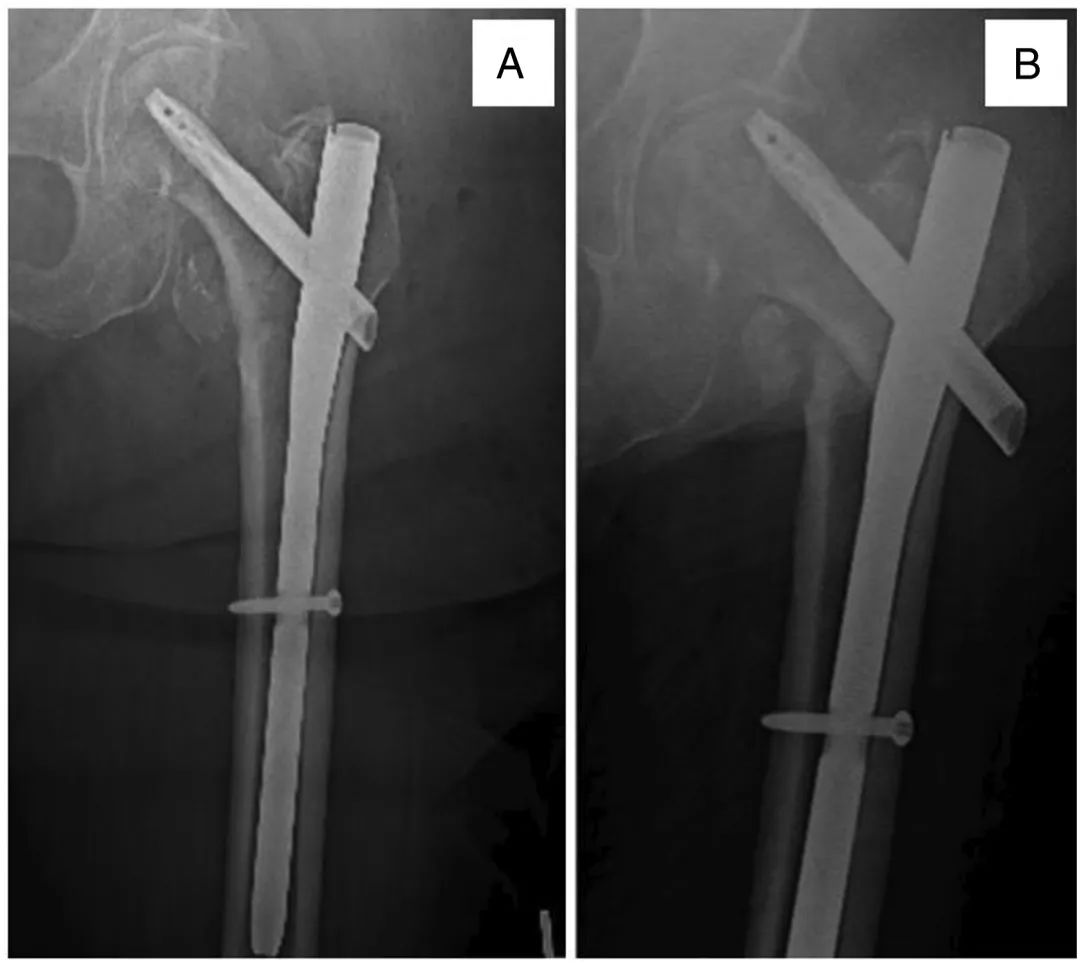

• Что делать, если внутренняя фиксация межротаторного перелома не удалась?

Что делать, если внутренняя фиксация межротаторного перелома не удалась?

2022-12-30

По оценкам, переломы шейки бедра ежегодно поражают 500 000 взрослых в Соединенных Штатах.Они оказывают огромное влияние на качество жизни, в настоящее время на их долю приходится 3-7% госпитальной летальности и годовая смертность 19,4-58%.Примерно половина всех переломов шейки бедра являются межвертельными (ИТ).